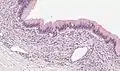

| Micrograph showing a mucinous cystadenoma of the ovary. H&E stain. | |

Mucinous cystadenoma is a benign cystic tumor lined by a mucinous epithelium.